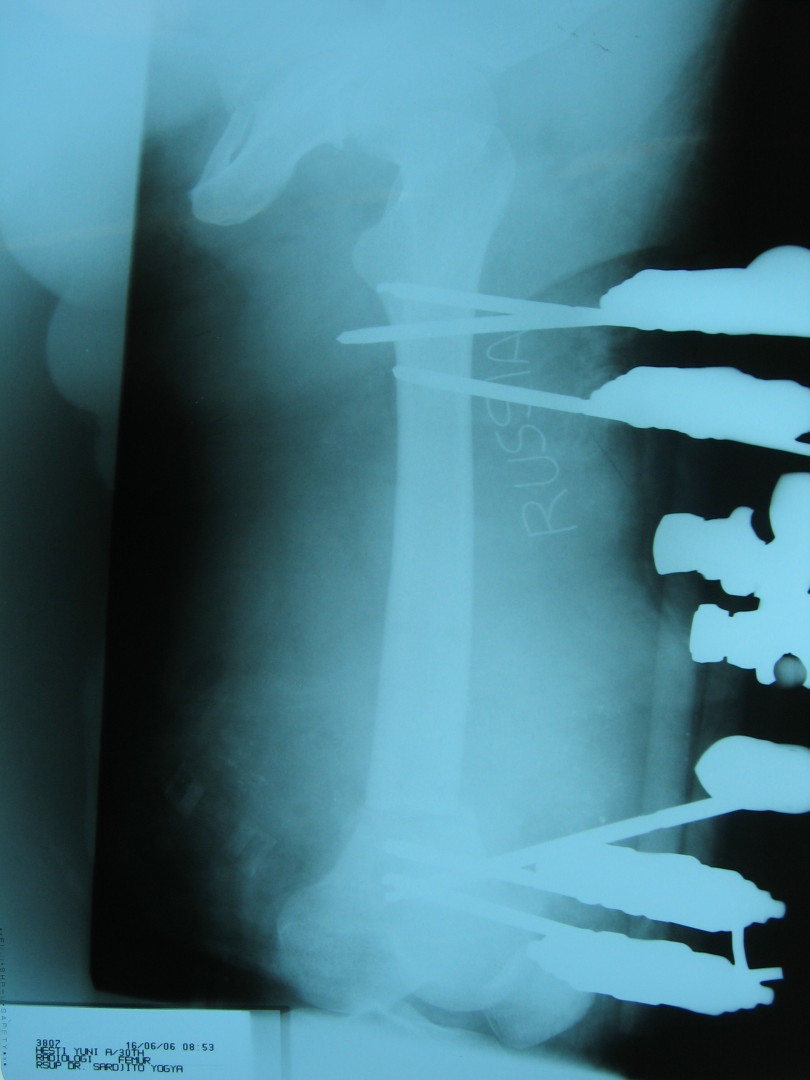

27 мая 2006 года Индонезию потрясло страшное землетрясение.

По сообщения информационных агентств за один день погибло более 4500 человек. Столько же людей получили ранения.

Мобильная бригада врачей НИИ неотложной детской хирургии и травматологии оперативно вылетела на место катастрофы.